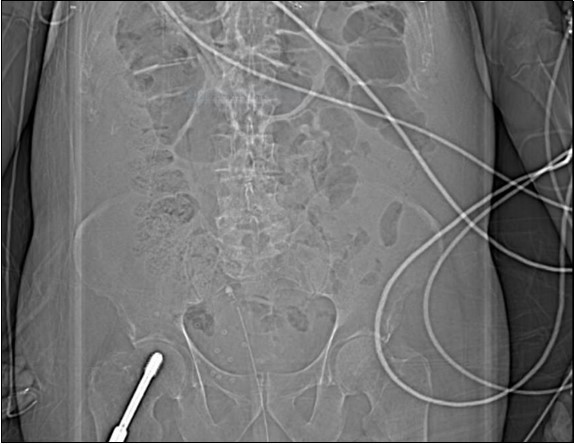

An urgent CT abdomen revealed a bladder perforation with the tip of the irrigating catheter situated in the abdominal cavity (Figure 1, Figure 2, Figure 3a,Figure 3b). This was most likely due to over-insertion of the 3-way catheter due to the extra force required because of the benign prostatic hypertrophy. He had therefore been receiving normal saline as ‘peritoneal dialysis’ with normal saline since insertion of the catheter. The catheter was withdrawn, and the patient made a full recovery.

Figure 1.coronal plane CT scout image

coronal plane CT scout image